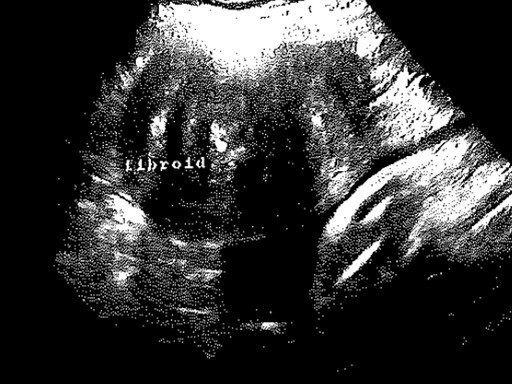

Sevasti Melissa Nolas will be the keynote speaker, and will talk about her most recent work through the following communication: “How to follow a fibroid: Multimodal approaches and methods to the more-than-human”.

"In 2013, I gave birth to my son by emergency caesarean section (C-section) under general anesthetic after a long labour. While not uncommon where I live—in the United Kingdom around 24% of deliveries result in an emergency C-section and C-sections account for 42% of overall births—the cause of this particular event was the presence in my womb of two benign tumours known, when they happen to be addressed, by their medical names, fibroids or myomas. Fibroids, while not always problematic, affect most women by age 50, are especially prevalent during the reproductive years, and can have considerable impact on a woman’s quality of life. However, what is known about fibroids is more theory than evidence making these fleshy objects mercurial despite the hardness and recalcitrance of their materiality. Easy to miss and hard to ignore, over the years, these bodies within a body have, somewhat unexpectedly, become a muse of sorts to me. Fecund objects, that have preoccupied a large part of my embodiment, fibroids have pushed me towards more creative, sensory, and multimodal ways of thinking and writing as I attempt to sketch out and fill in their more-than-human contours and contexts for a broader audience. The talk—part interdisciplinary scholarly intervention, part performance—draws on my essay ‘Incongruent Gestures’, published by Cache.ch in November 2024 in the collection Radical Health, as well as subsequent work-in-progress in which I further follow the fibroid through creative non-fiction writing, photography, and art as well as attempts to locate it in archives and historical texts. In particular, and taking my cue from the fibroid itself, I explore the ways in which a multimodal approach has not only been necessary but essential in order to better grasp this enigmatic mass that is so resistant to representation in all meanings of that word."